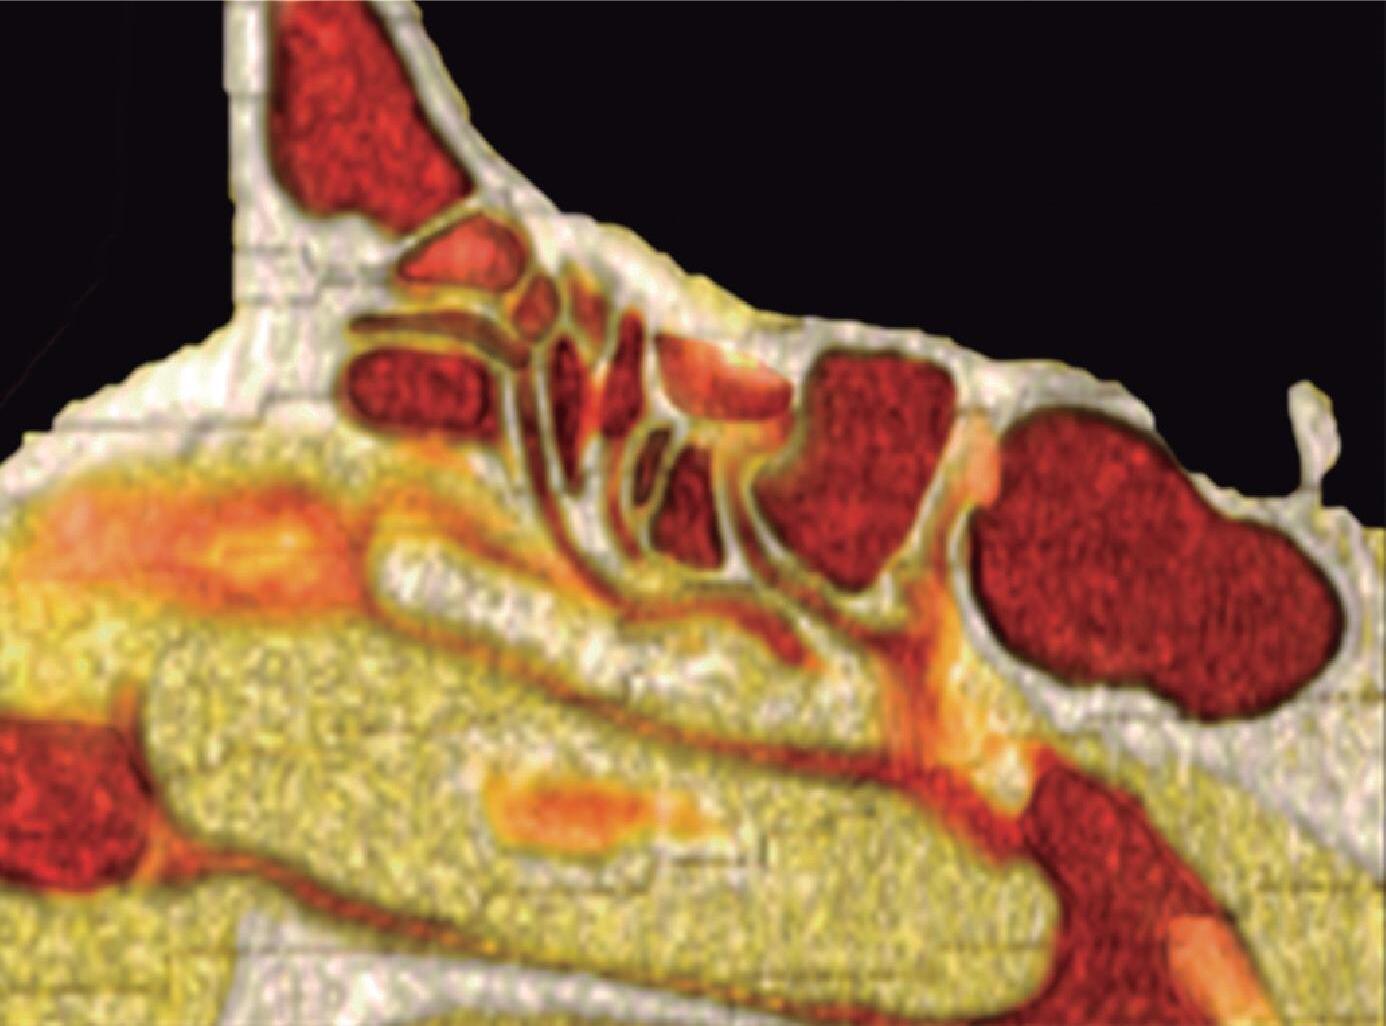

1-4. TC e reconstrução 3D com destaque para estrutura etmoidal (em vermelho), funcionando como câmaras de baixa pressão para drenagem do seio maxilar.

1-7. TC com reconstrução 3D mostrando em vermelho apenas o seio etmoidal e não o osso etmoidal, e sua relação com a fossa nasal, o seio maxilar, órbita e fossa anterior.

1-8. Osso etmoidal e seio etmoidal (amarelo) observar o aspecto incompleto do teto do seio etmoidal que será coberto pelo osso frontal (rosa).

Este complexo anatômico chamado seio etmoidal, controla a pressão e o fluxo aéreo que penetra nos verdadeiros seios paranasais e pode ser interpretado como um sistema de câmaras aerodinâmicas de baixa pressão cuja topografia particular faz dele o centro anatomofuncional do aparelho rinossinusal.